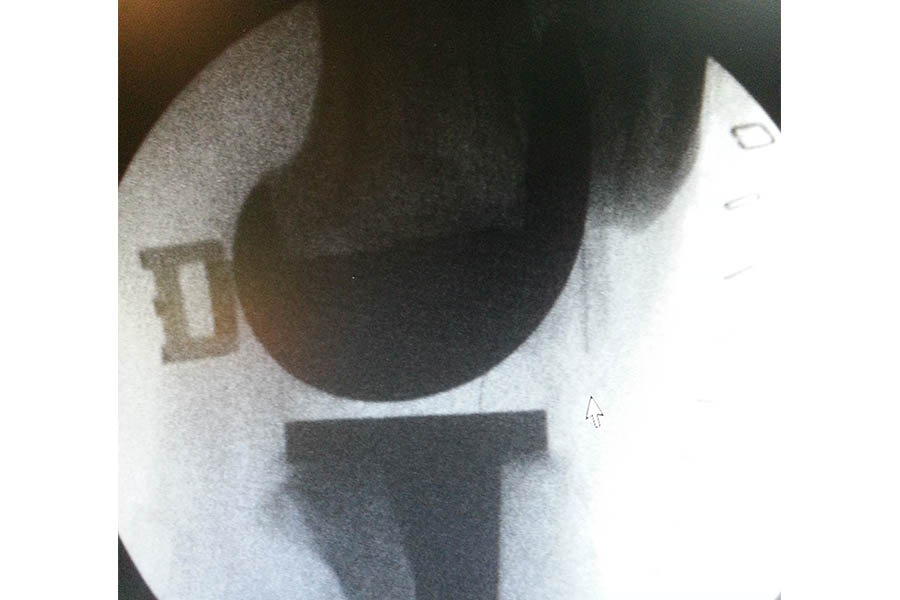

Complicated Joint Replacement

Case 1